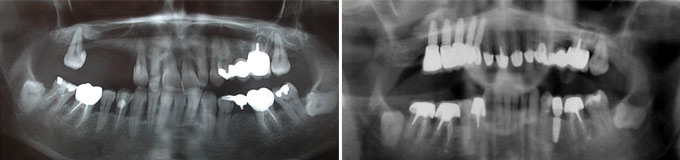

J’ai des caries partout, des dents manquantes, je veux l’idéal.

Toutes les dents manquantes sont remplacées et le sourire refait.

Une situation de pertes dentaires multiples et infections sous des racines naturelles.

Final : traitements de racines effectués et dents manquantes remplacées.